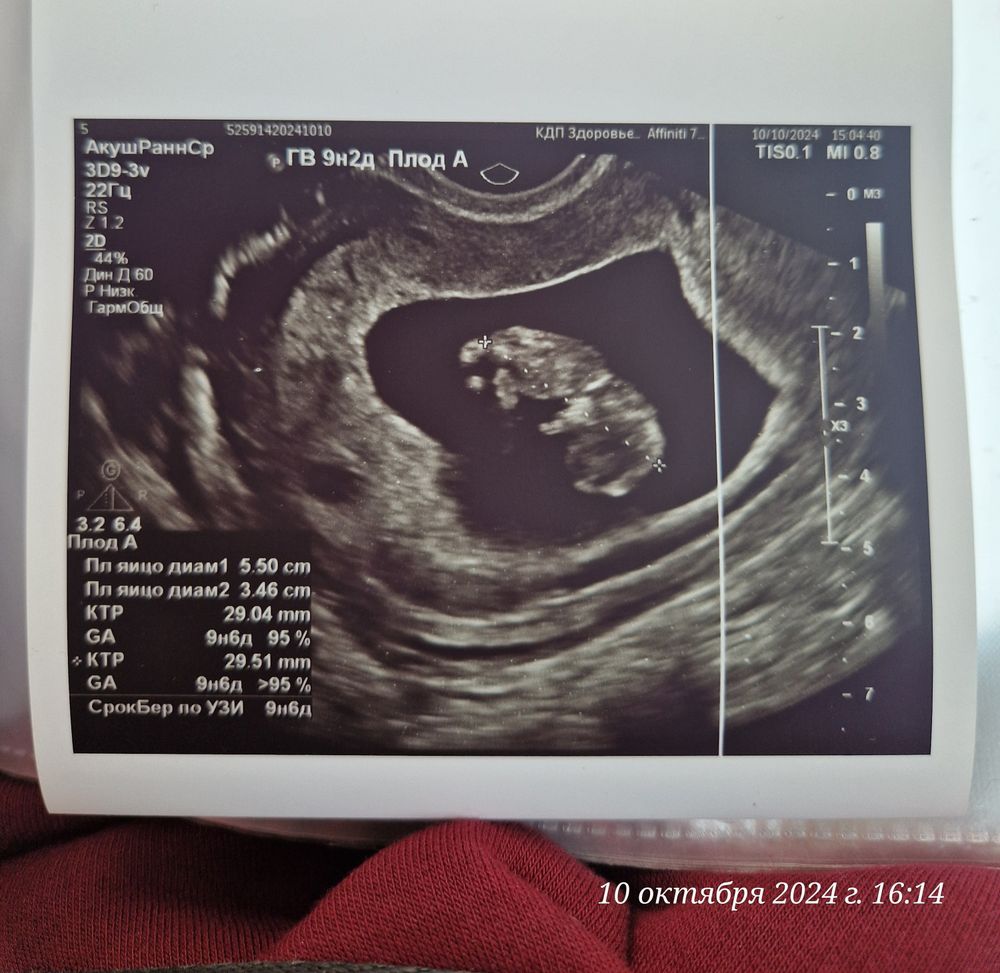

Дарина в Зачатие год Покидайте фото узи в 9 недель 🙏🏻 УЗИ Девочки у кого остались или есть фоточки покидайте пожалуйста! Хочу сходить в 9 неделек на узи, с монитором, хочется узнать как что там примерно видно будет Посмотрите еще 20 записей на эту тему Лучший ответ Елена 9н 2д двойня 02.11.2024 Ответить Отменить Ответить Таня Орозова 01.11.2024 Ответить Екатерина 01.11.2024 Ответить Екатерина Екатерина, чуть больше, 9,5 01.11.2024 Ответить Евгения 9+3 недели 01.11.2024 Ответить ЛисАлис 01.11.2024 Ответить Екатерина 01.11.2024 Ответить Екатерина Екатерина, 9 недель ровно, первое УЗИ 01.11.2024 Ответить Екатерина Екатерина, ножки попка к верху 😄 01.11.2024 Ответить Дарья 01.11.2024 Ответить Евгения Дарья , а вам делали трансвагинально или абдоминально? 01.11.2024 Ответить Дарья Евгения, трансвагинально . А вот 10 недель узи) 01.11.2024 Ответить Евгения Дарья , ух ты) а мне абдоминально делали😁 как в этот раз будут не знаю, пойду в другое место 01.11.2024 Ответить Евгения 01.11.2024 Ответить Мира В интернете нашла)) 01.11.2024 Ответить Девочки подскажите !! Пост нытья Чаты Беременных Выберите чат: Январята-2026 Февралята-2026 Мартята-2026 Апрелята-2026 Майчата-2026 Июнята-2026 Июлята-2026 Августята-2026